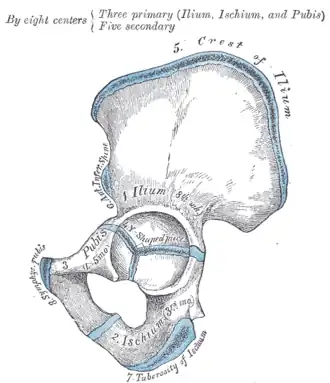

Тазовая кость (лат. os coxae) — это обозначение для парной кости правой и левой, которые относятся к поясу нижних конечностей, а вместе с крестцом и копчиком образуют таз. Используется также название безымянные кости. Каждая из тазовых костей в свою очередь образована тремя составляющими: подвздошной костью, седалищной костью и лобковой костью, которые соединяются посредством хряща в области вертлужной впадины, служащей местом соединения тазовой кости с бедренной. В возрасте 14-16 лет эти три кости срастаются, образуя единую тазовую кость.

Подвздошная кость (лат. os ilium) составляет ближайшую к позвоночнику часть пояса задних конечностей или таза, сочленяющуюся с крестцовыми позвонками. Она ясно выражена уже у амфибий. У человека она сочленяется крестцовой костью, являющейся результатом слияния 5 позвонков, и в области вертлужной впадины, служащей для помещения головки бедра, срастается с двумя другими тазовыми костями: седалищной и лобковой. Верхний край подвздошной кости человека закруглён, передний и задний образуют по два выступа (лат. spinae anterior superior, ant. inferior, posterior superior, post. inferior), а на своей внутренней и наружной поверхности она имеет изогнутое линейное возвышение (linea arcuata inferior et exterior).

Седалищная кость (лат. os ischii) — одна из костей пояса задних или нижних конечностей, иначе таза. Она ясно выражена уже у амфибий. У человека она состоит из следующих частей: тело, которое соединяется сверху с подвздошной костью, а спереди с лобковой горизонтальной ветвью и вместе с этими костями образует тазовую кость (os coxae). В месте соединения этих костей находится вертлужная впадина (acetabulum) для приёма бедренной головки. От тела вниз на задней части отходит нисходящая ветвь (ramus descendens), образующая на нижнезаднем углу седалищный бугор (Tuberculum ossis ischii) и продолжающаяся вперёд и вверх в виде восходящей ветви (ramus ascendens). Последняя с нисходящей ветвью лобковой кости, и таким образом между телом седалищной кости, её обеими ветвями и обеими ветвями лобковой образуется овальной формы отверстие (foramen obturatum sivo ovale).

Лобковая кость (лат. os pubis) — одна из трёх костей, образующих при сращении тазовую кость. Состоит из тела и двух ветвей. Ветви и тело лобковой кости образуют запирательное отверстие (foramen obturatoris), закрытое запирательной мембраной. Две лобковые кости, срастаясь, образуют переднюю стенку таза.

Тазовые кости новорождённого (слева) и ребёнка 12-13 лет, синим отмечена хрящевая ткань